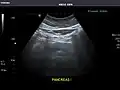

Pancreas -

Pancreas: Visualized portions unremarkable.